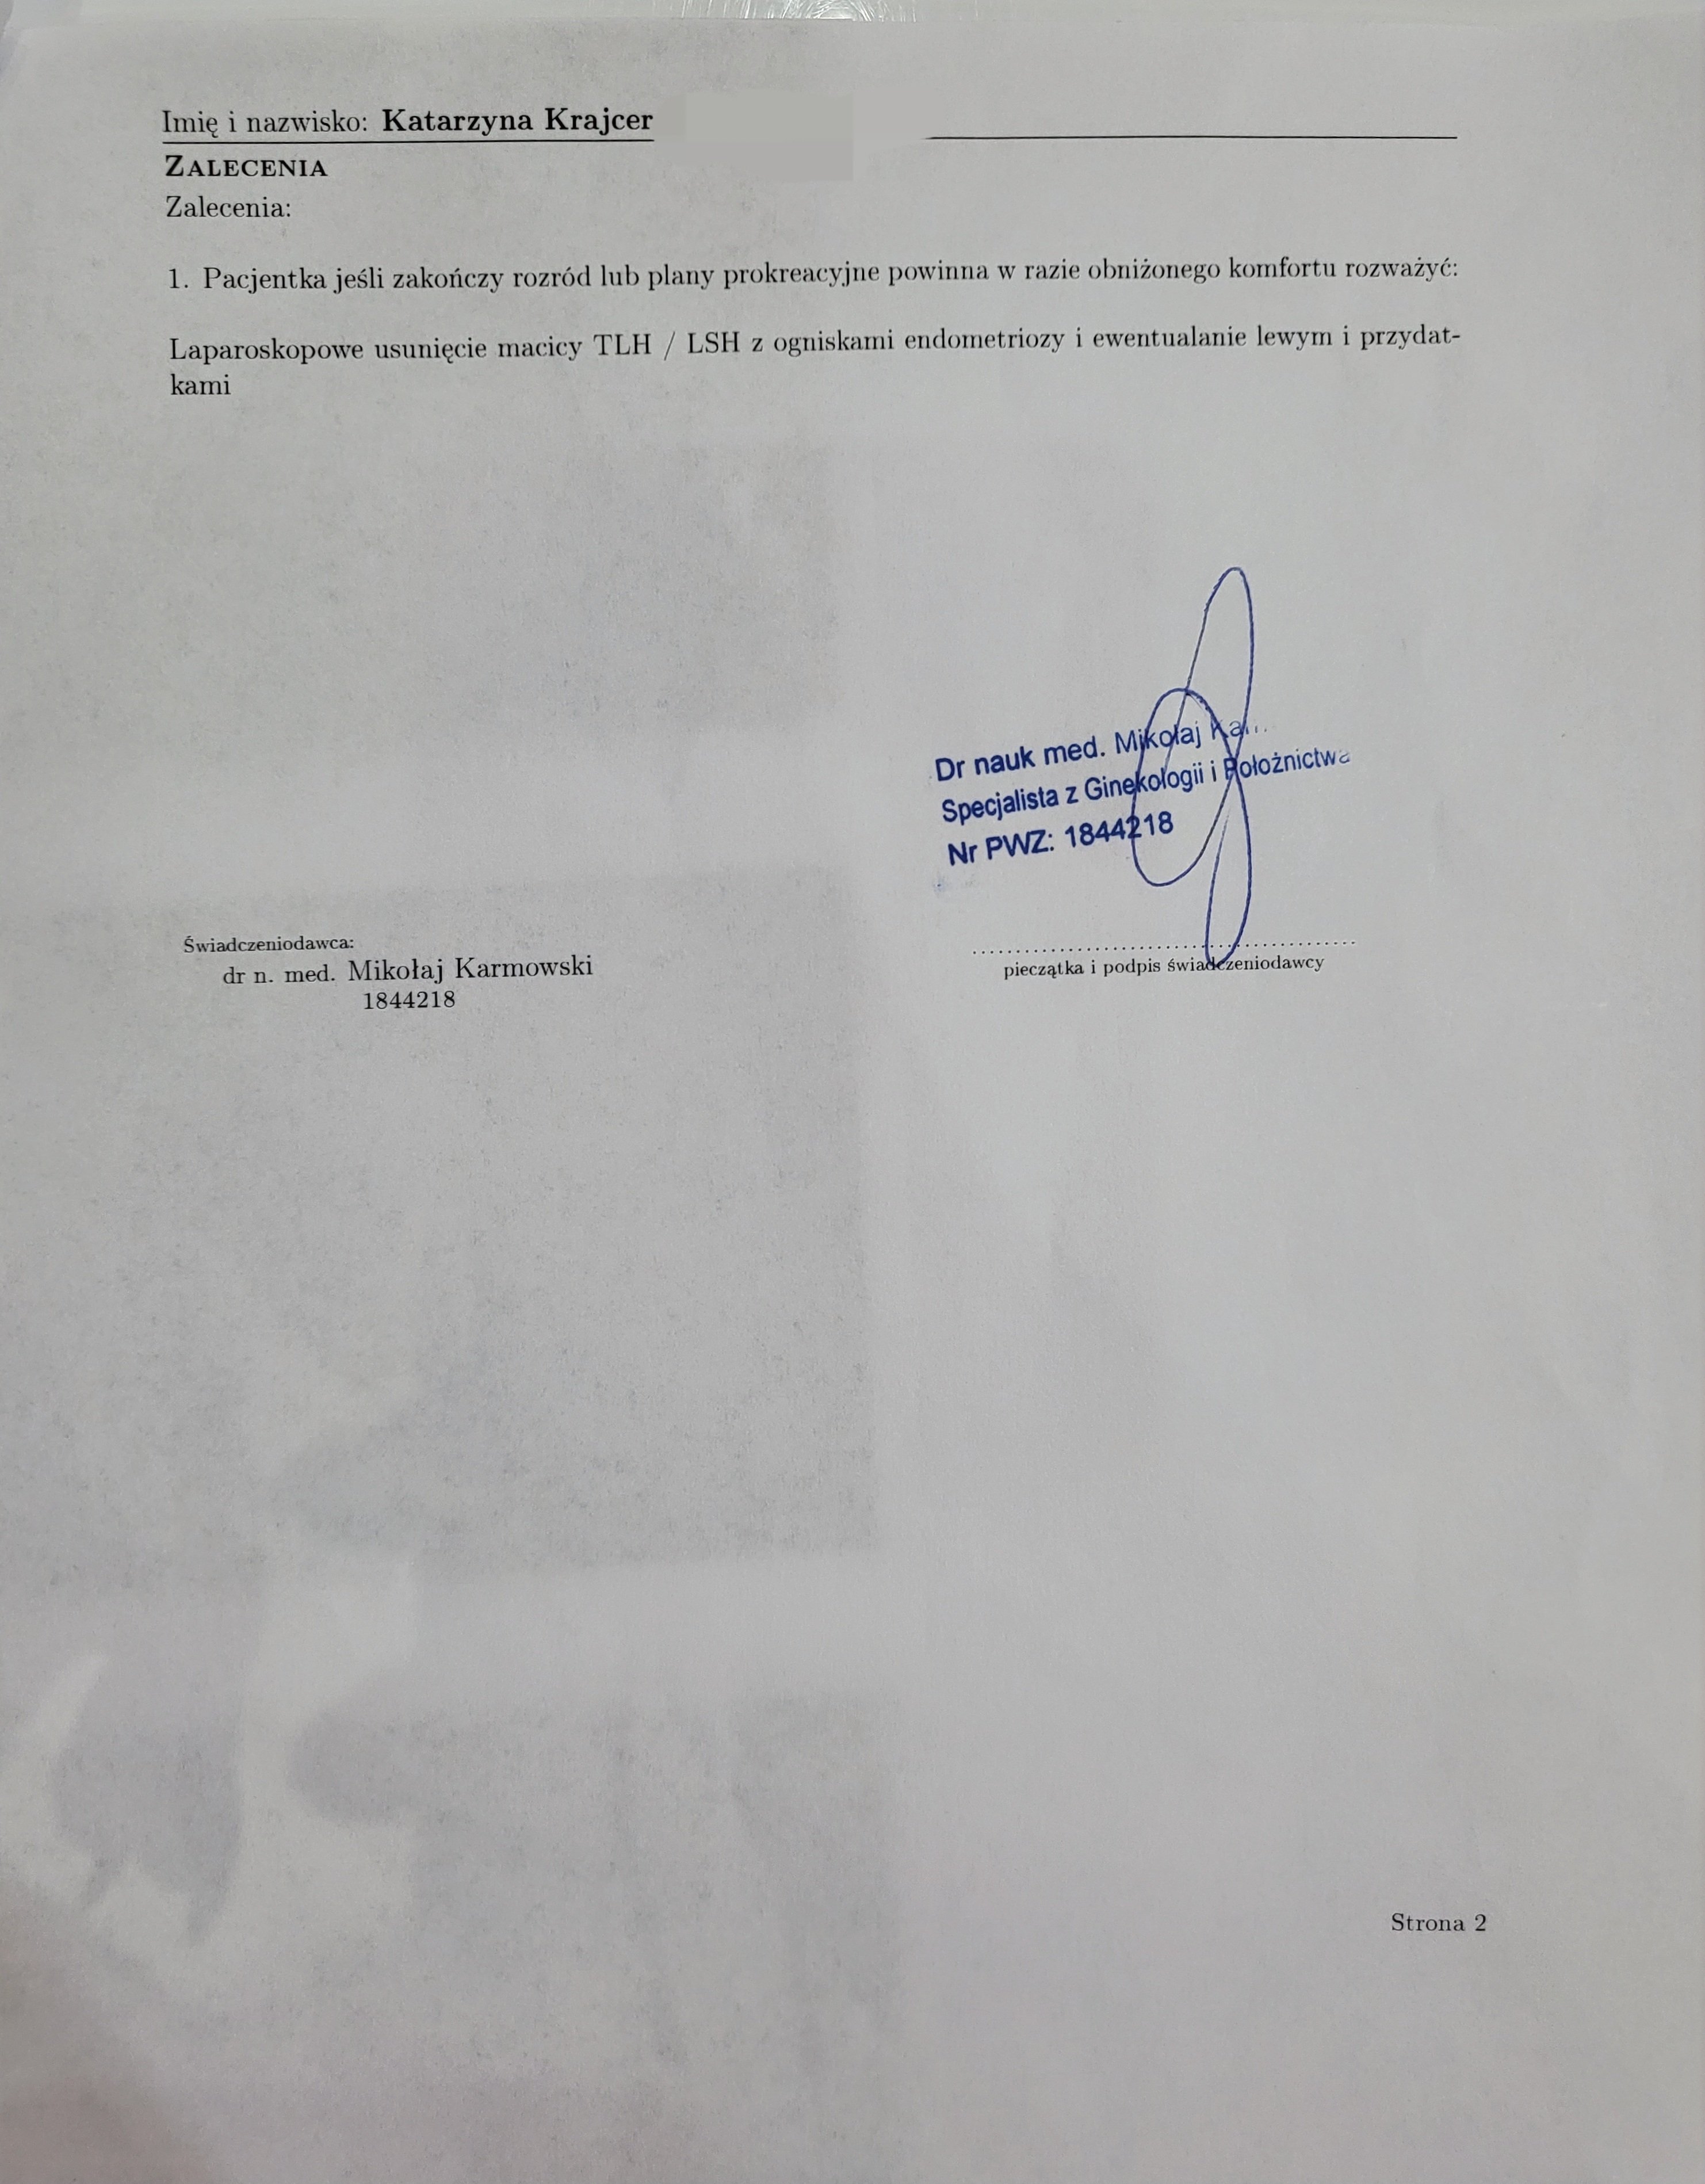

Dr Mikołaj Karmowski – ginekolog specjalista w dziedzinie leczenia endometriozy, postawił diagnozę endometrioza i adenomioza.

Postanowiłam umówić się na wizytę, która miała miejsce 04.03.2024r.

Dr Karmowski prosił, abym usiadła na fotelu i po dokładnym przeprowadzeniu badania opowiedział o wszystkim co mi dolegało. W końcu na swojej drodze spotkałam lekarza, który chce i potrafi mi pomóc.

Po wizycie w Instytucie Endometriozy zdecydowałam się napisać informacje swojej ginekolog o endometriozie i adenomiozie oraz o konieczności usunięcia całej macicy wraz z lewym jajnikiem.

Pani doktor zadzwoniła z informacją o zebraniu konsylium w mojej sprawie.

Na spotkaniu oprócz mojej pani doktor był inny ginekolog-położnik. Od lekarzy dowiedziałam się, że po usunięciu macicy nie będę kobietą, człowiekiem. Nagle wpadli na pomysł przeleczenia mnie hormonalnie dwoma lekami ( o nich wspominał również dr Karmowski, ze mój przypadek jest tak zaawansowany, że jedyną i skuteczna metodą pozbycia się bólu jest operacja). Szkoda, że miejscowi ginekolodzy nie zaproponowali mi takiego leczenia, gdy nie było jeszcze za późno.

Podczas konsylium poinformowano mnie, że nie usunę macicy na NFZ, ponieważ mam tylko jedno dziecko i jestem bardzo młoda.